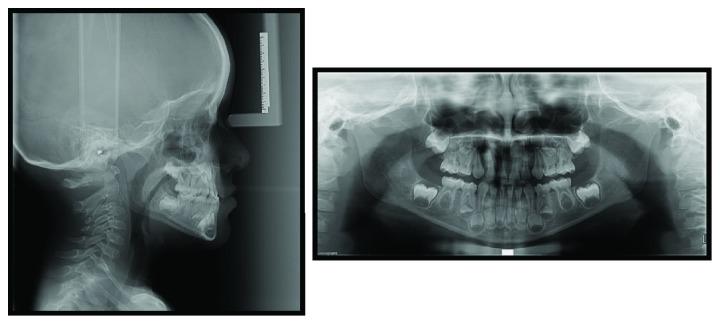

The prevalence of class III malocclusion ranged from 0 to 26% in different populations. Many types of treatments have been described in dental literature. The results of early treatment have been positive. The purpose of this report is to describe the case of a four-year-old patient with class III malocclusion who received an innovative treatment using direct anterior tracks. This therapy efficiently obtained immediate improvement of profile and occlusal relationships.

在不同人群中,III类错牙合畸形的患病率在0%至26%之间。牙科文献中描述了多种治疗方法。早期治疗的结果是积极的。本报告的目的是描述一名患有III类错牙合畸形的四岁患者的病例,该患者接受了使用直接前方导板的创新治疗。这种治疗有效地立即改善了面部轮廓和咬合关系。